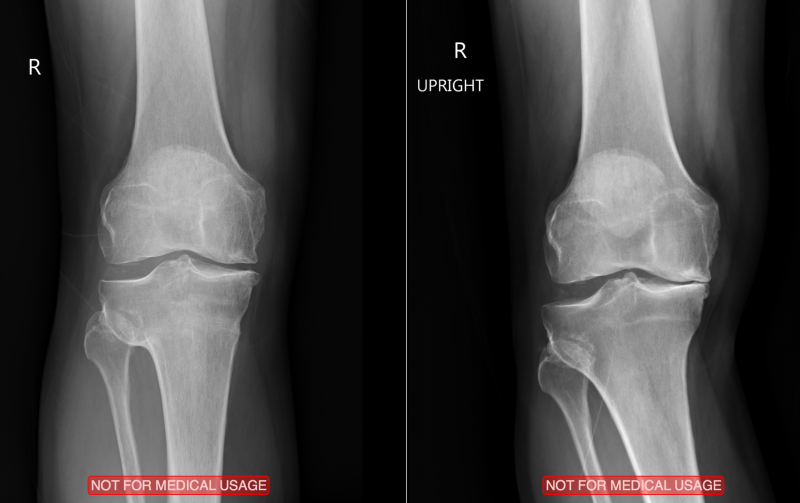

6 out of 8 looking at the X-ray said " HTO ".... High Tibial Osteotomy.

basically - Medial Meniscus removed 30 years ago, sports injury. As you can imagine now, the knee is painful, and because no meniscus, there is some bow leg

Hospital gives X-ray, and got OsiriX (to view orig X-rays )..... cool to see space has gone from 0 to 3.6mm already. But not sure if cause cartilage growth, or just because muscles and everything more loose cause not using leg for 5 weeks.